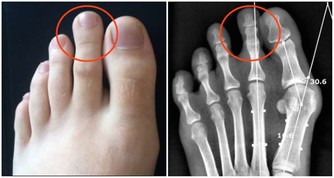

許多患者只有血清尿酸鹽濃度的增高而沒有臨床症狀,只有在發生關節炎時才稱為痛風。痛風的病理基礎是高尿酸血症,正常人血尿酸值是男性2.4-7mg/dL,女性1.6-5.2mg/dL。

當體液中尿酸濃度超過此值時,將因過剩而在組織中沉積,這種尿酸鹽的結晶沉積在關節滑膜、關節骨、軟骨而導致痛風性關節炎,沉積在皮下則形成痛風石。中西醫均會要求痛風患者不可以攝取高普林食物,然而這些食物可以說是最起碼的美食,要痛風病患完全不吃這些食物,說真的,這種治療的犧牲代價還不小呢!